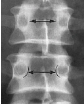

Q what is the name of this measurement? and what is the average + range?

A: Van Akkerveekans measurement of Lumbar instability

assesses lumbar instability by measuring horizontal displacement. There should be less than 1.5 mm of displacement.